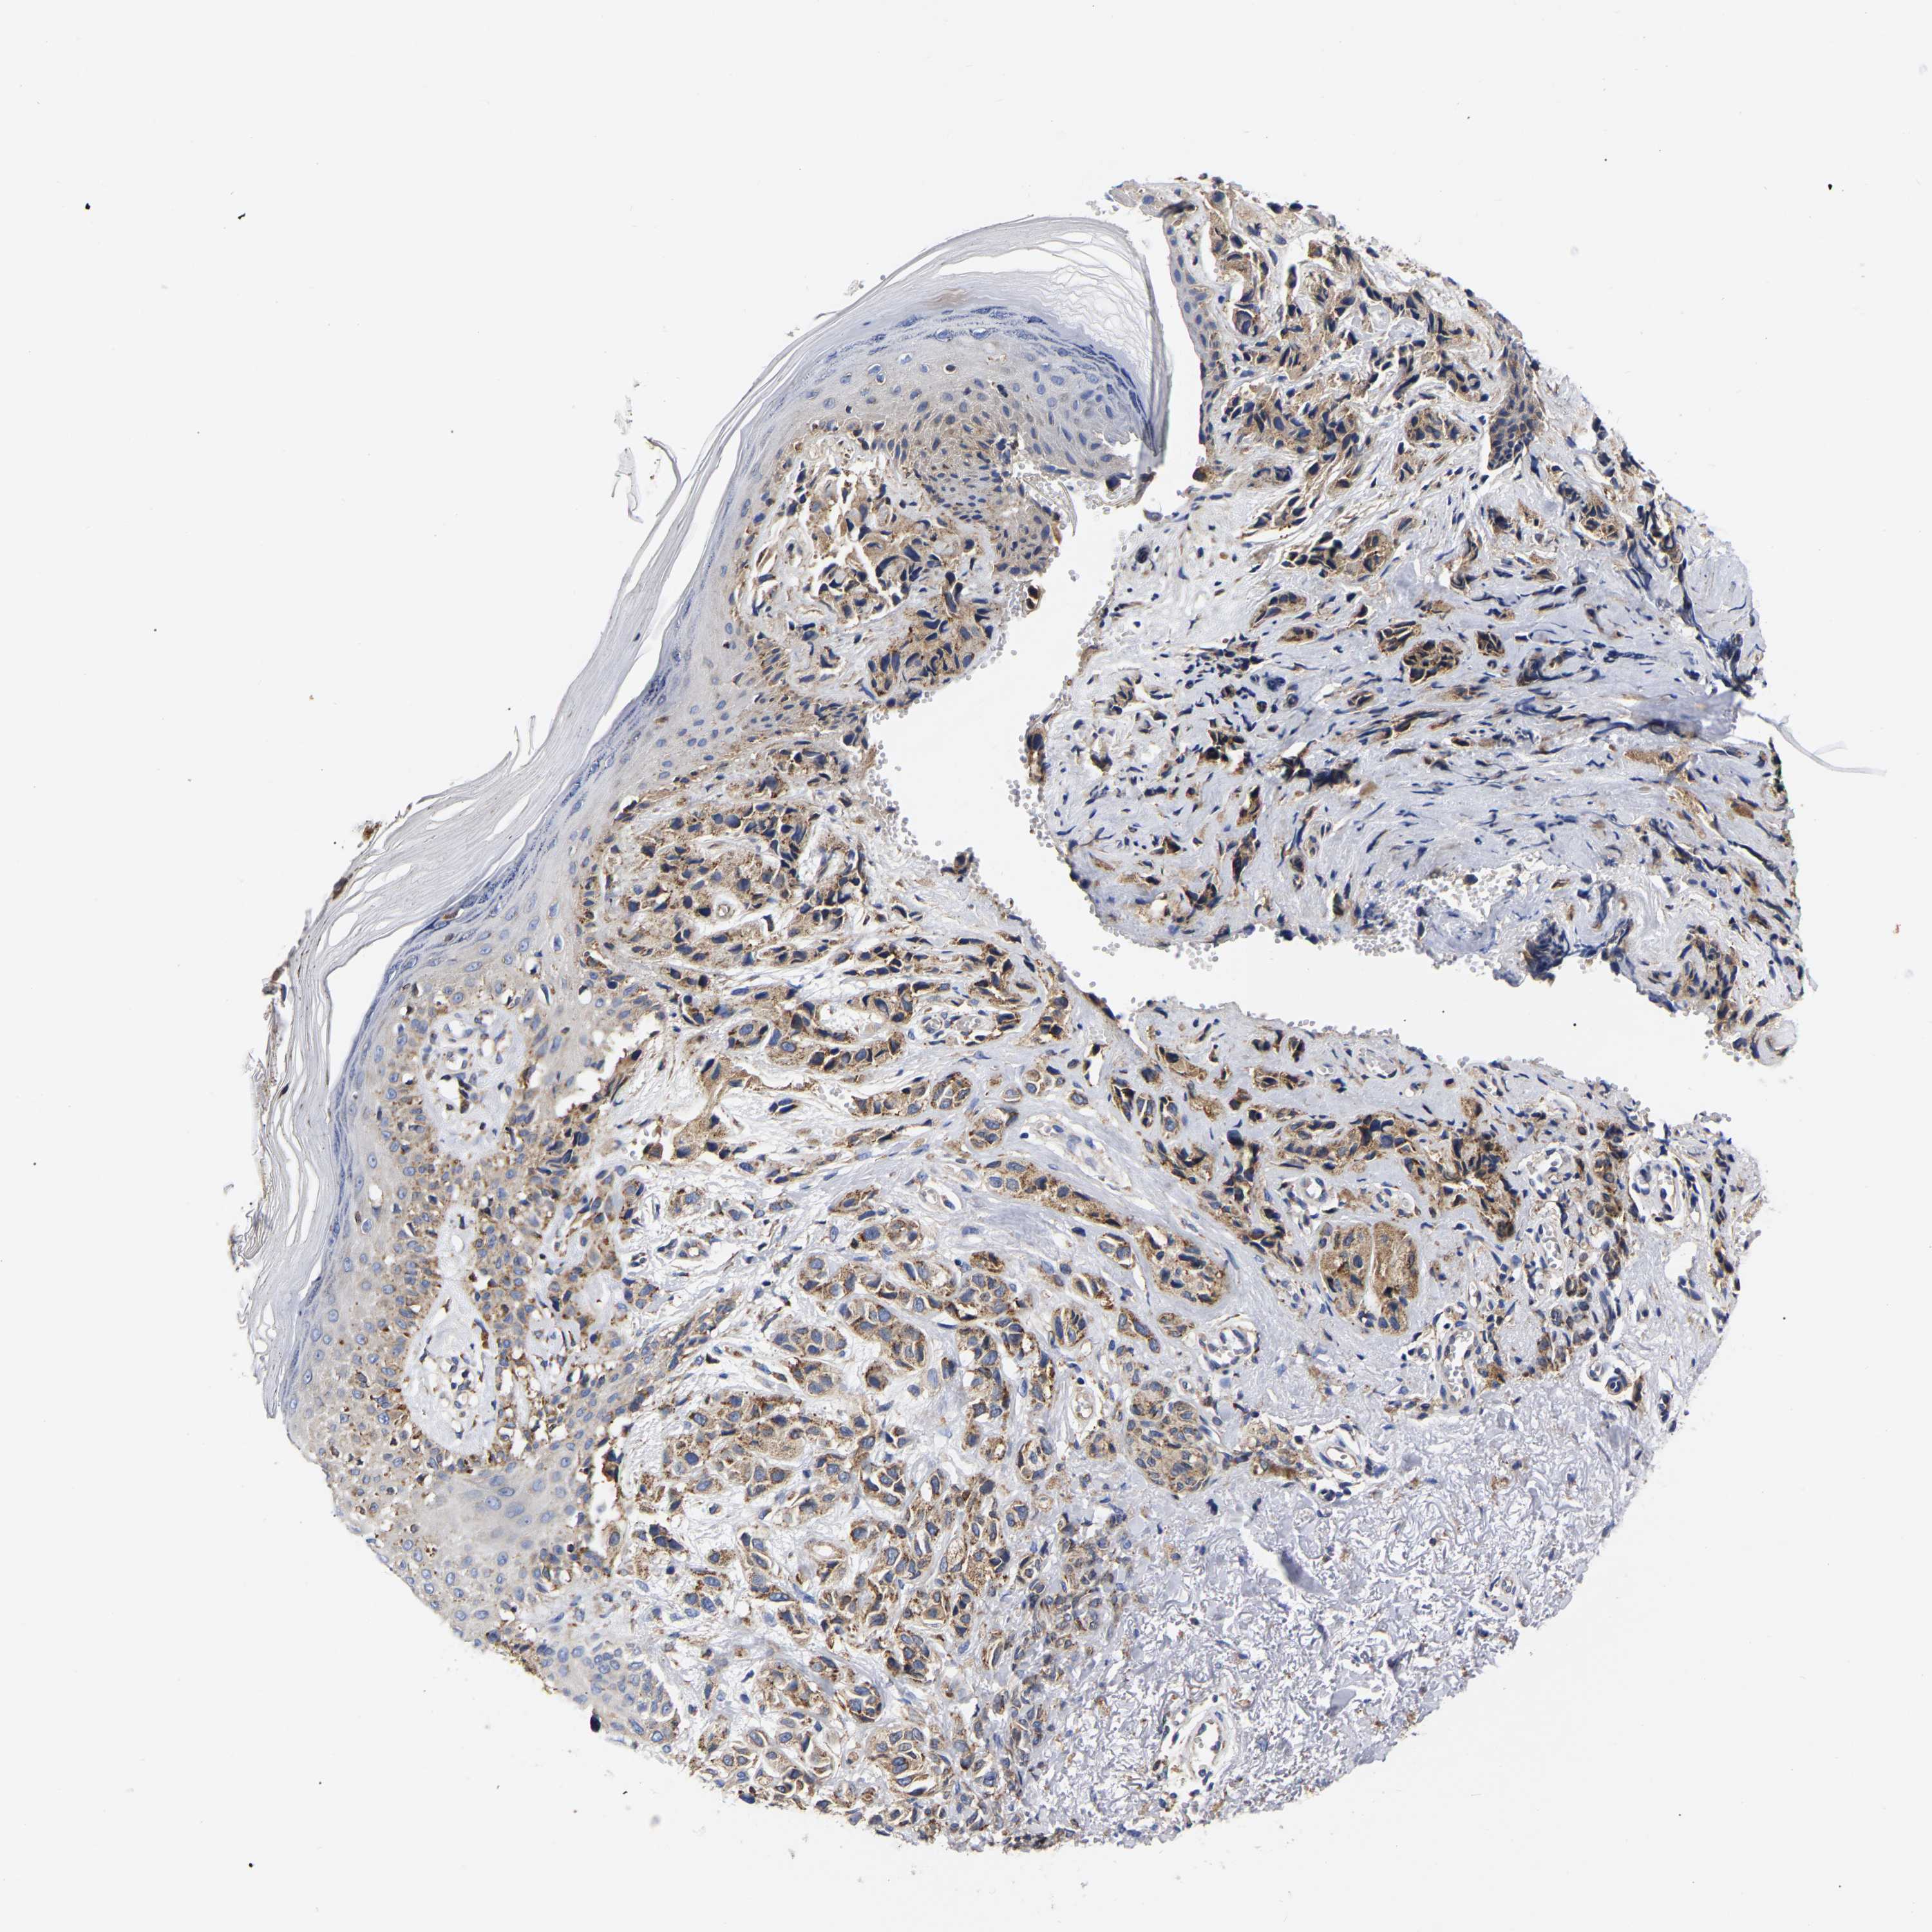

MELANOMA - Protein expressioni

A mouse-over function shows sample information and annotation data. Click on an image to view it in a full screen mode. Samples can be filtered based on level of antibody staining by selecting one or several of the following categories: high, medium, low and not detected. The assay and annotation is described here.

Note that samples used for immunohistochemistry by the Human Protein Atlas do not correspond to samples in the TCGA dataset.

Antibody stainingi

Antibody staining in the annotated cell types in the current human tissue is reported as not detected, low, medium, or high, based on conventional immunohistochemistry profiling in selected tissues. This score is based on the combination of the staining intensity and fraction of stained cells.

Each image is clickable and will lead to virtual microscopy that enables deeper exploration of all samples and also displays staining intensity scores, fraction scores and subcellular localization as well as patient and tissue information for each sample.

Antibody HPA018453

Antibody HPA019055

Antibody HPA028849

Antibody CAB034170

Staining

High

Medium

Low

Not detected

Intensity

Strong

Moderate

Weak

Negative

Quantity

>75%

75%-25%

<25%

None

Location

Nuclear

Cytoplasmic/membranous

Cytoplasmic/membranous,nuclear

Malignant melanoma, NOS

Malignant melanoma, Metastatic site